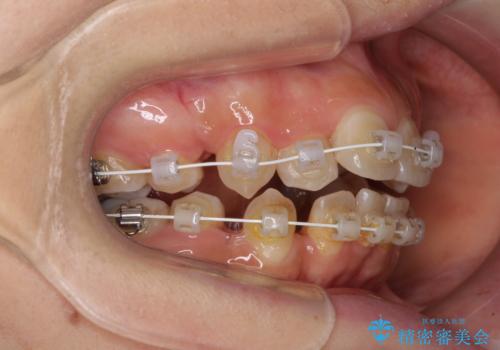

- 矯正装置

- 審美装置

- 治療期間

- 2年

- 治療回数

- 10-30回